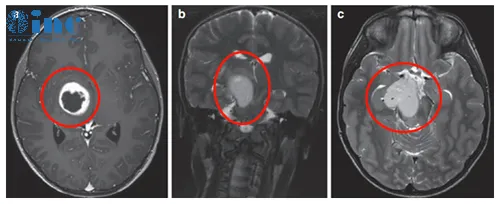

患者情况:左面部、上肢和下肢有3周的急性病史,持续轻微口齿不清三个月以上。他还有多处咖啡色的斑点和腋窝雀斑。被诊断患有注意缺陷多动障碍,这些症状可以归因于器质性病因。(下图a、b)轴位MRI造影剂及冠状面T2-WI显示一个环形增强的右侧丘脑结节肿瘤。

治疗过程:Rutka教授考虑根据其病情进展制定综合治疗方案,先行经颞中回经脑室入路次全切除肿瘤,组织学为WHO I级毛细胞星形细胞瘤,BRAF重复融合状态为阴性。免疫组化检测BRAF V600E、H3K27M阴性。基因测试证实了NF1基因的变异。术后严密随访患儿术后情况。

治疗后情况:6个月后的影像显示丘脑部分切除和中脑的小肿瘤残留,因此,Rutka教授根据其病情发展量身定制辅助治疗计划,患儿对放疗反应良好。

术后6个月显示肿瘤次全切除